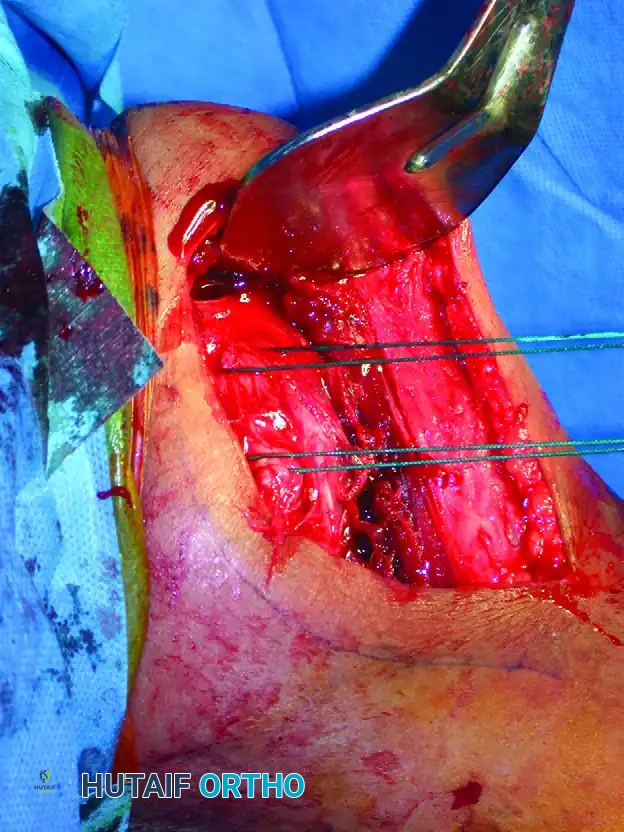

- Tuberosity Control: Place heavy, non-absorbable sutures (e.g., #2 or #5 FiberWire) through the rotator cuff tendons at their insertion sites on the greater and lesser tuberosities. These sutures act as traction tags to manipulate the tuberosity fragments out of the subacromial space and reduce them to the shaft.

Open reduction and internal fixation of a proximal humeral shaft fracture. Sutures placed in the rotator cuff are actively used to assist in the reduction of the tuberosities.

Sutures utilized for the precise reduction and provisional fixation of comminuted tuberosity fragments.